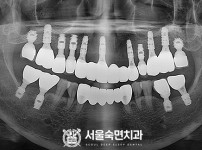

임플란트-전후사진1